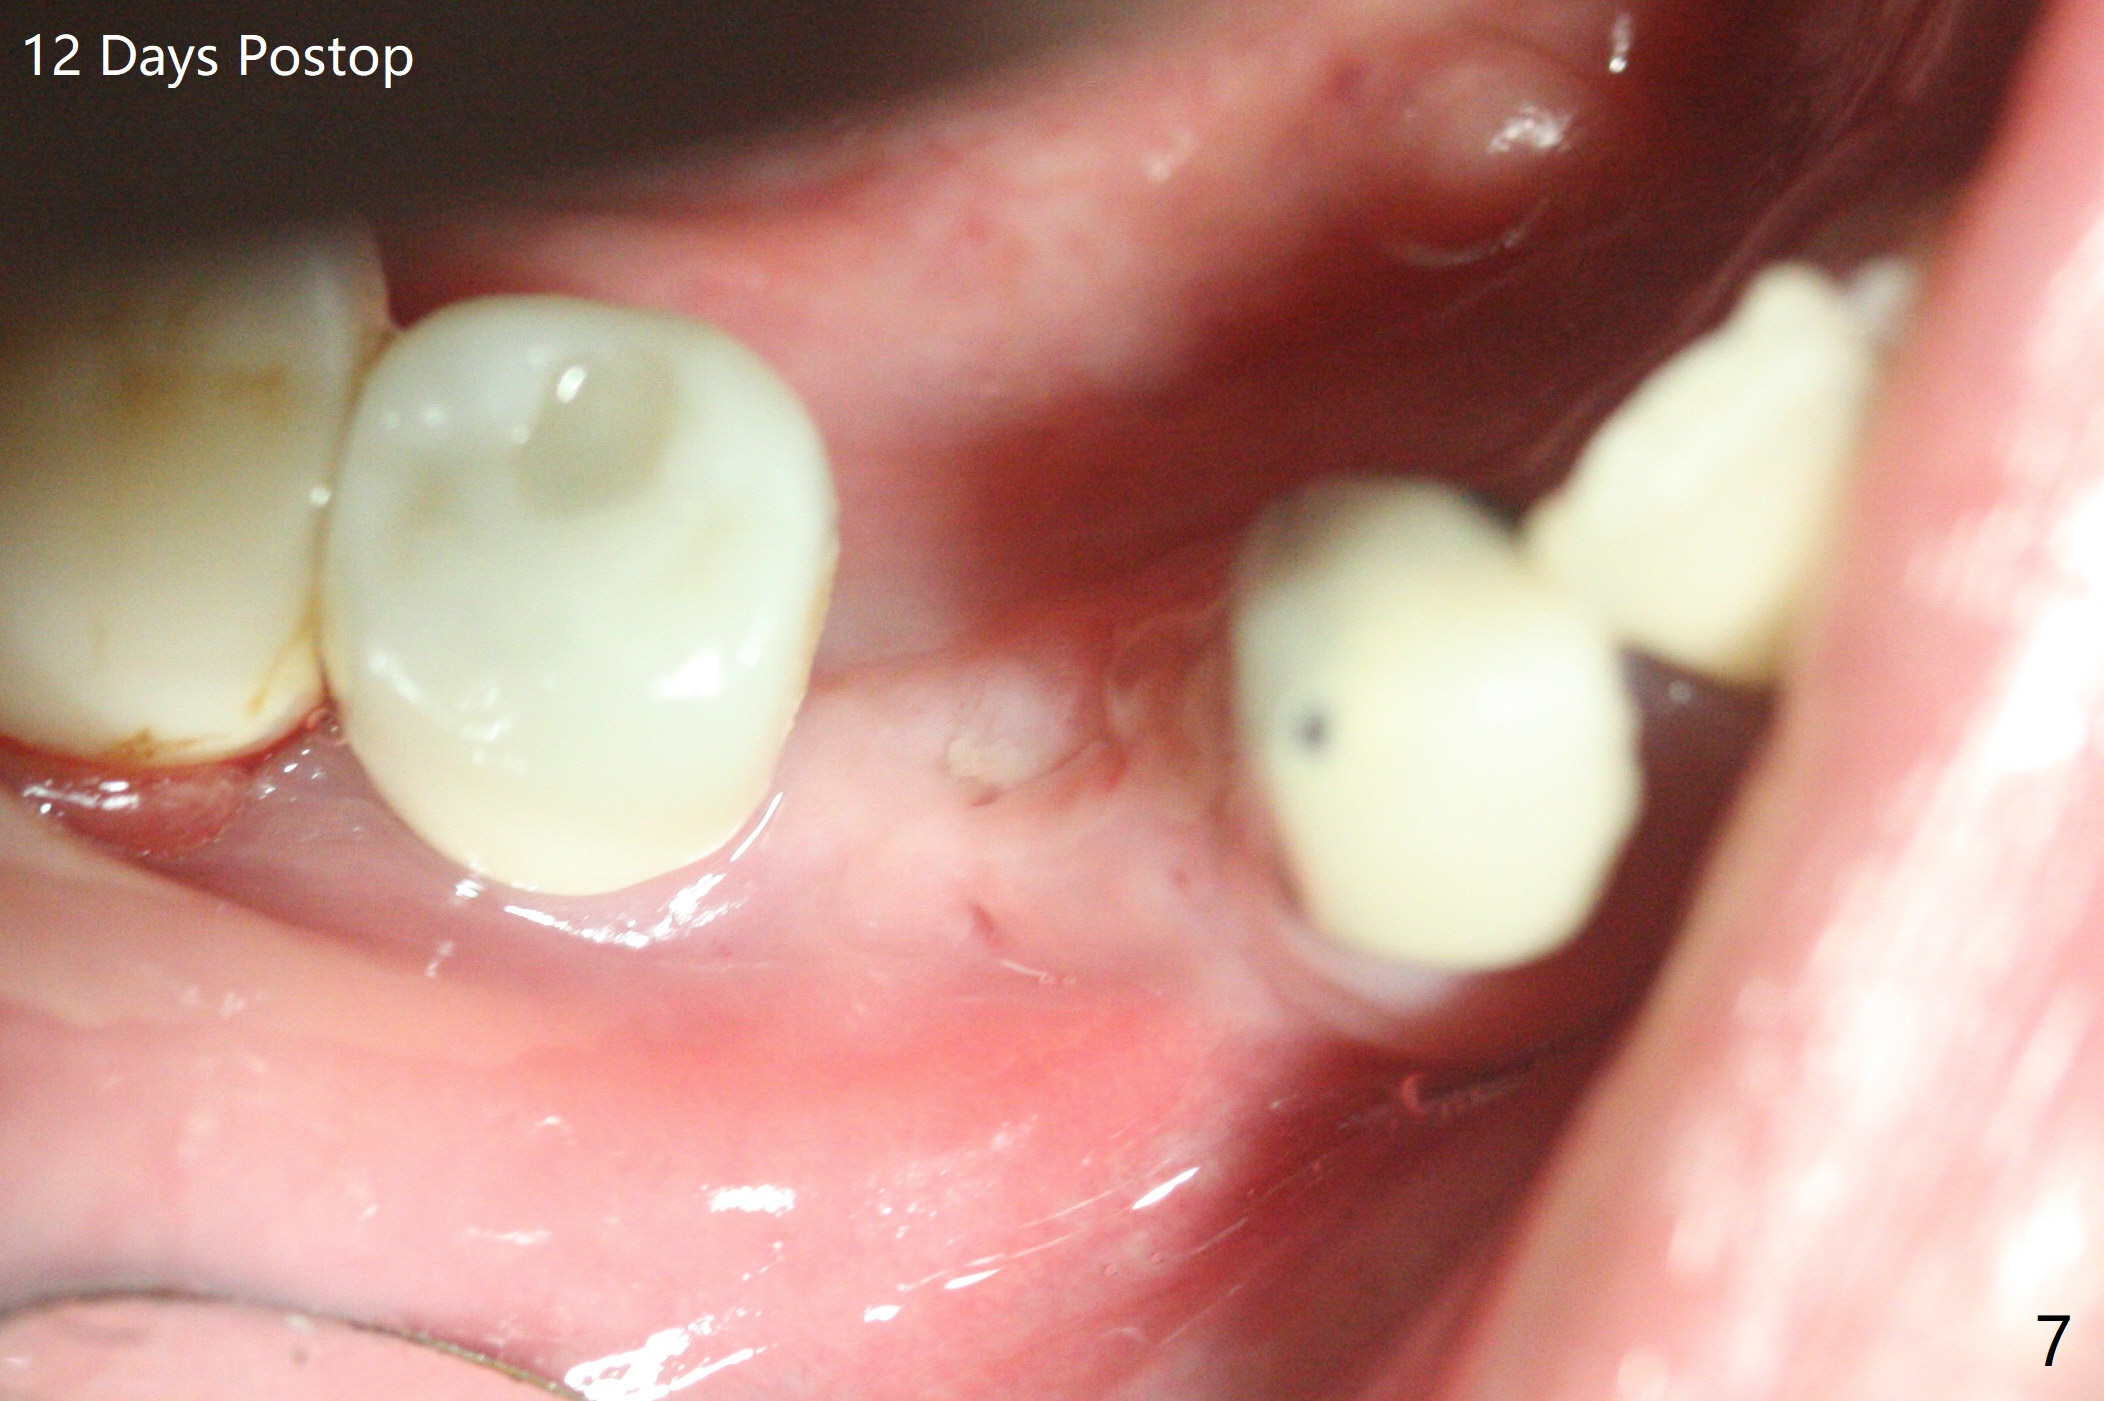

52岁男右下4植体脱落三天回到诊所(图一),植牙创尚未闭锁,顺着开口去除肉芽组织,冲洗,充填皮质骨骨粉(图二,三),颊侧骨板外形恢复(图四,五:*)。重新植入UF植体(5)颊侧还有薄颊侧骨板(图五:>),而6植体周围骨质吸收(图六),植骨好像有希望,植体还在牙槽骨范围,也有利于5植体生存。术后12天伤口愈合(图七)。尽管使用水枪,仍有6植体周围炎,需要治疗(图八)。由于右侧手术,病人不得不用左侧咀嚼,他认为左下4松动,无法挽救。术后3.5个月牙槽嵴和角化龈缩小(图九),需要切开使用导板。术后3.5个月骨粉高度明显下降(图十)。只能植入4x8.5毫米植体(图十一)。